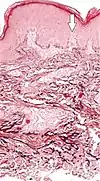

Elastosis is the buildup of elastin in tissues, and is a form of degenerative disease.[10] There are a multitude of causes, but the most commons cause is actinic elastosis of the skin, also known as solar elastosis, which is caused by prolonged and excessive sun exposure, a process known as photoaging. Uncommon causes of skin elastosis include elastosis perforans serpiginosa, perforating calcific elastosis and linear focal elastosis.[10]

| Actinic elastosis (most common, also called solar elastosis) |

Elastin replacing collagen fibers of the papillary dermis and reticular dermis |  |